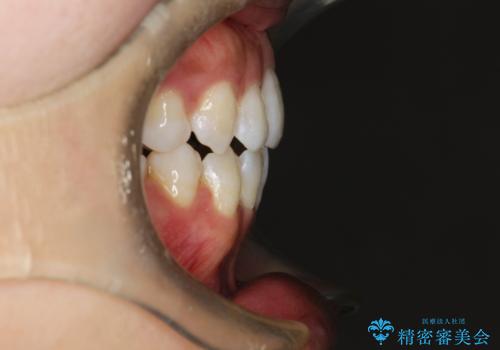

- 前歯がガタガタなのと、前歯でものが噛めないことを主訴に来院されました。

前歯の叢生があり、上下の前歯が接触していない開咬という状態でした。

左側の上下の前から4番目の歯を抜歯して、矯正することとしました。